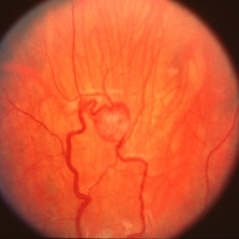

Fundus photo immediately after laser photocoagulation treatment of the retinal angioma OD in Von Hippel-Lindau.

Condition/keywords: laser photocoagulation, retinal angioma, Von Hippel-Lindau